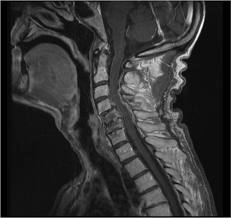

Hernias de disco

La hernia discal es una enfermedad en la que parte del disco intervertebral (núcleo pulposo) se desplaza hacia la raíz nerviosa la comprime y produce lesiones neurológicas derivadas de esta lesión.